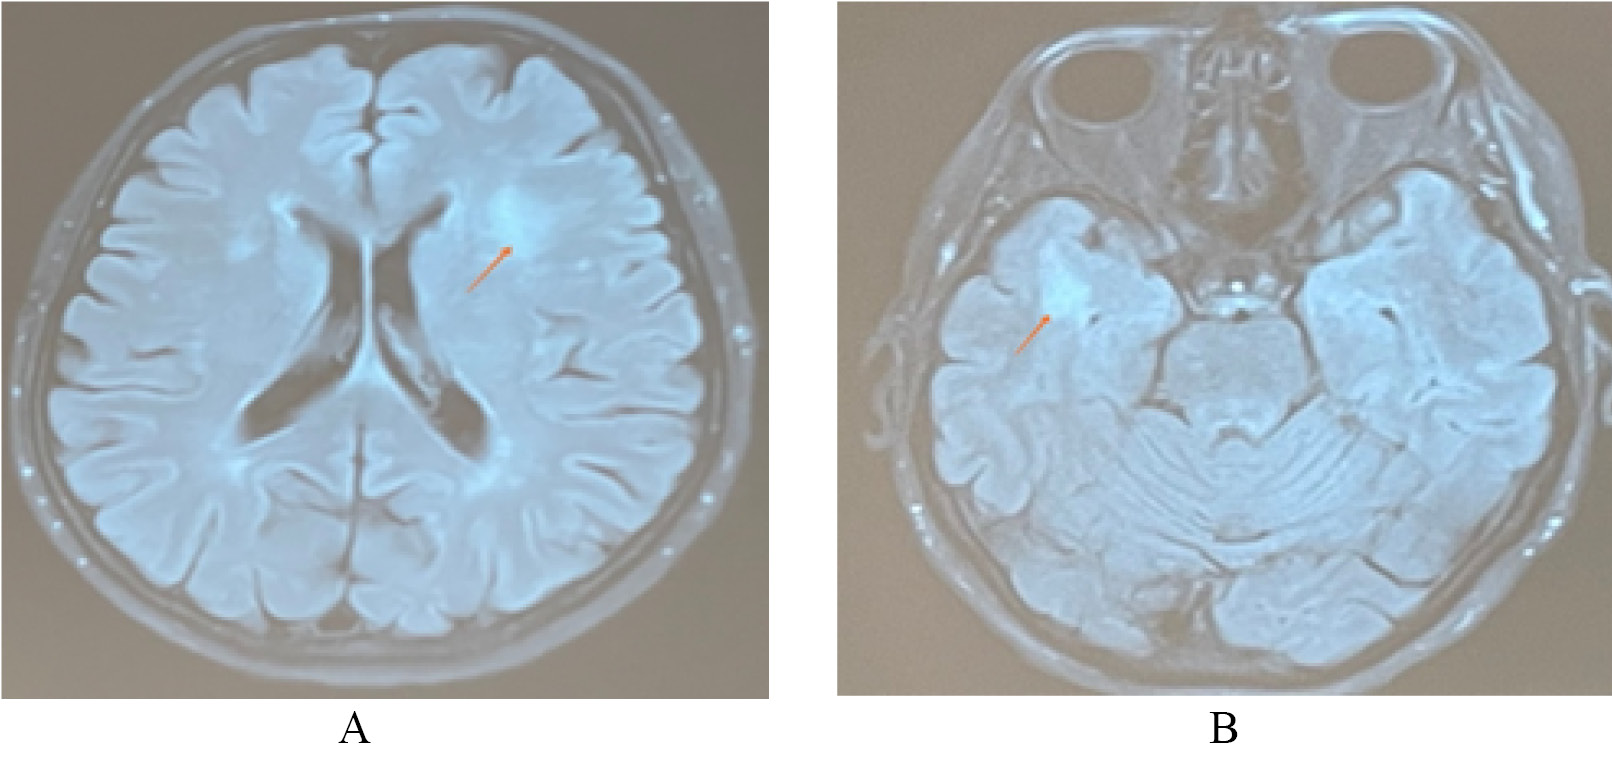

МРТ головного мозга с внутривенным контрастированием от 23.03.2021. Субкортикально и паравентрикулярно в белом веществе головного мозга в височных, лобных и теменных долях (от 4 до 8 мм), в левой лобной доле (16×14 мм), в правой височной доле (до 20×13 мм), в области базальных ядер (до 3 мм) визуализируются множественные очаги глиоза с нечёткими контурами, склонные к слиянию, характеризующиеся гиперинтенсивным сигналом на Т2-взвешенных изображениях (ВИ), изоинтенсивным на Т1-ВИ, без перифокального отёка и масс-эффекта. Очаги не имеют признаков ограничения и магнитно-резонансной (МР) диффузии, не накапливают контрастное вещество (рис. 2).

Рис. 2. Очаги гиперинтенсивного магнитно-резоненсного сигнала на Т2-взвешенном изображении и импульсная последовательность FLAIR в правой височной доле (Б); в белом веществе лобных долей

Заключение. МР-картина множественных очаговых изменений головного мозга дистрофического и дисциркуляторного характера, без признаков ограничения МР-диффузии и накопления контрастного вещества. Умеренная наружная заместительная гидроцефалия. Учитывая относительно молодой возраст пациентки и выраженные изменения белого вещества головного мозга, помимо ранних морфологических проявлений дисциркуляторной энцефалопатии, необходимо исключить наличие генетически детерминированной артериолопатии по типу ЦАДАСИЛ (поражение височных долей, ранний клинический признак — мигрень, снижение памяти). Демиелинизирующий процесс вне стадии активности — наименее вероятен (очаги в области мозолистого тела отсутствуют).